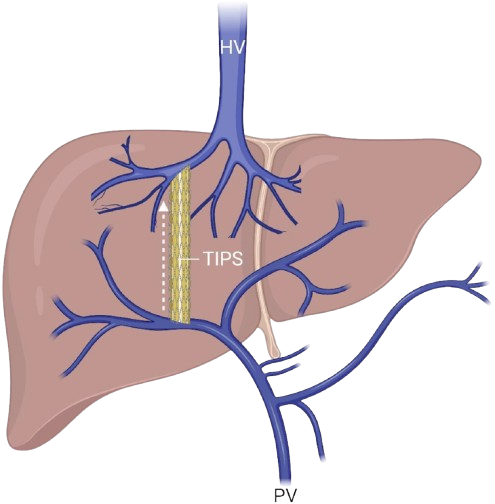

Portal Hypertension & Shunt Surgery

Surgical shunts to relieve high portal vein pressure.

Portal Hypertension

Advanced procedures for portal vein pressure relief.